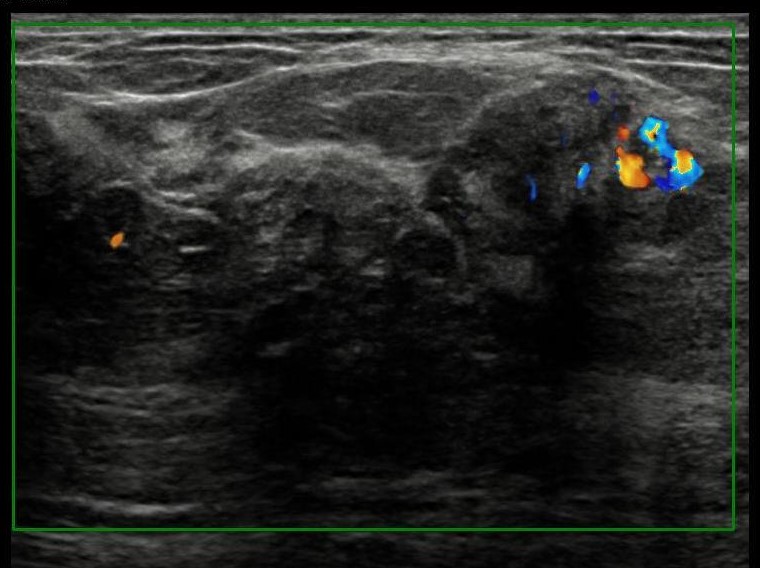

The most common cause of skin metastases in adult women is primary breast carcinoma, which comprises about 70% of cases [1]. Skin metastases have non-specific clinical appearances, making it challenging to differentiate them from other benign conditions [1]. We present a case of a 52-year-old female with type II diabetes and a three-month history of refractory skin lesions who did not respond to anti-inflammatory treatment. The patient subsequently complained of a right breast lump, evaluation of which led to the diagnosis of bilateral synchronous invasive lobular carcinoma.